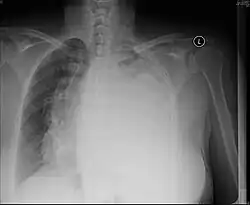

Pleural effusion

.jpg)

A pleural effusion is an accumulation of fluid inside the pleural space. If this collection of fluid gets large enough, it can also push structures in the chest away from it and cause a mediastinal shift. However, a pleural effusion can also pull the mediastinal structure towards itself. If this is the case, then there is an underlying condition causing the collapse of the lung on that side. An example is a tumor obstructing a bronchus and causing lung collapse and pleural effusion.[3]